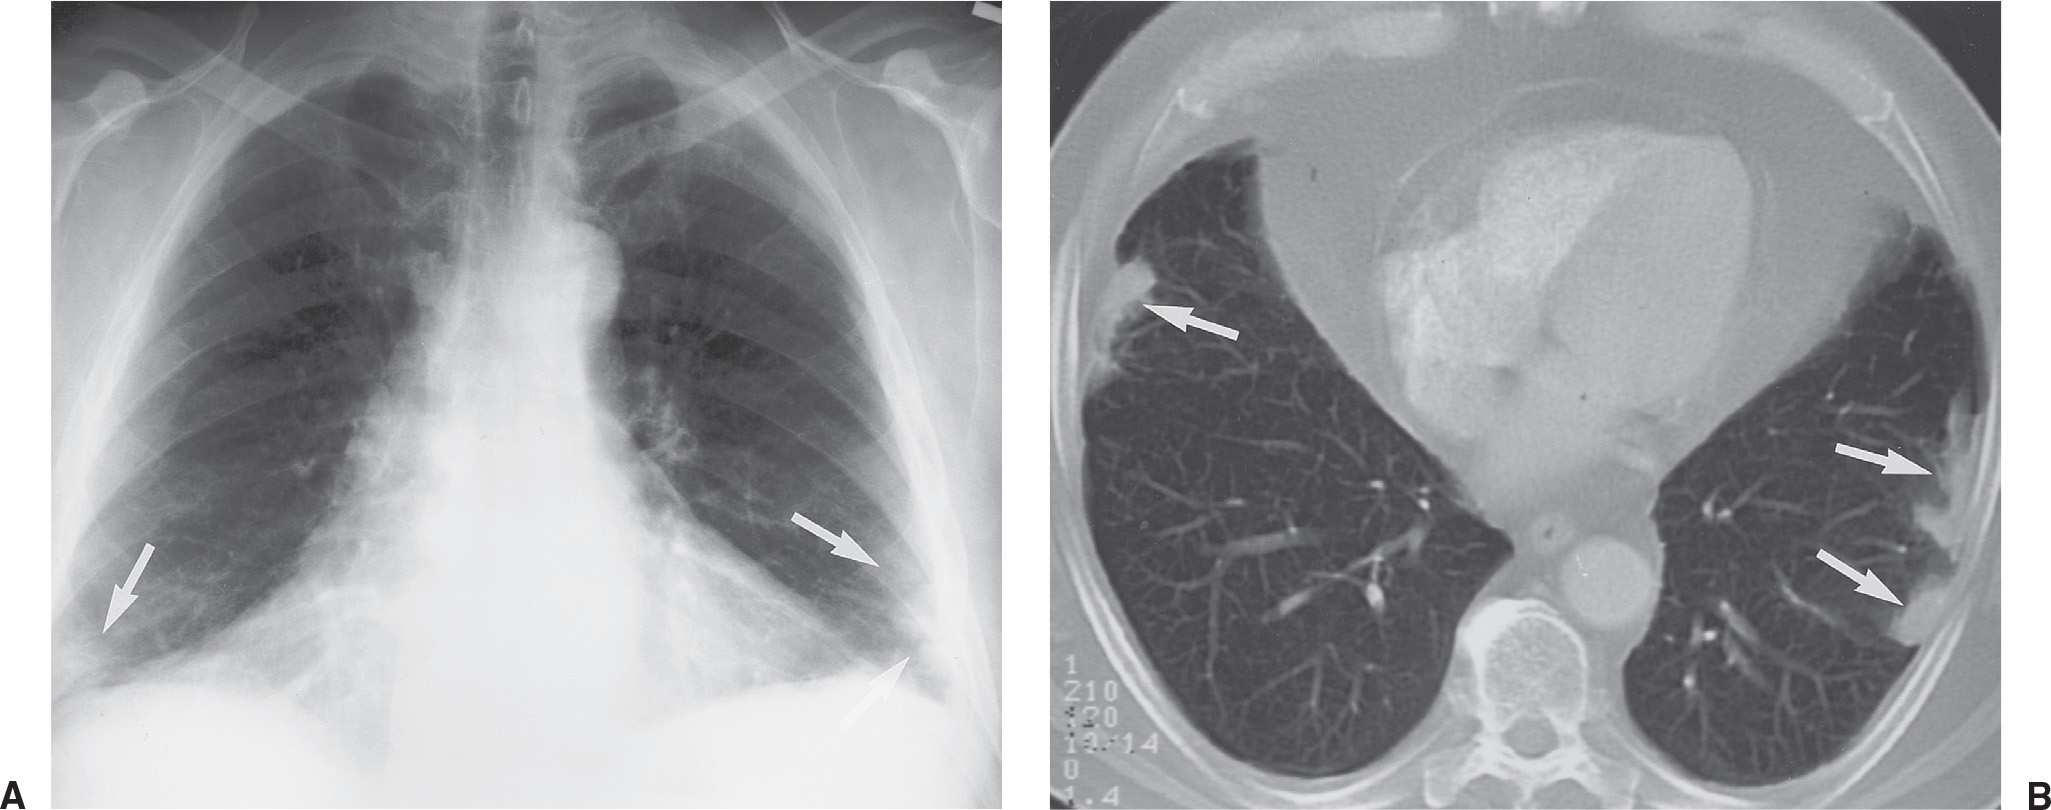

Chest X Ray Interpretation pleural effusion Radiology Imaging Pleural Tag Sign Radiology Juxtapleural lung nodules can be defined by their location within 15 mm of a pleural surface. Pleural tags refer to slender bridges of soft tissue seen on ct scans that extend between masses in the lungs and the pleura. By univariate analysis and multivariable adjustment, surgical history, tumour marker (tm), number of pleural tags, length of solid contact and obstructive. Pleural Tag Sign Radiology.

Hampton hump and Palla sign Radiographic signs of pulmonary embolism Pleural Tag Sign Radiology Juxtapleural lung nodules can be defined by their location within 15 mm of a pleural surface. Intrapulmonary lymph nodes are typically. By univariate analysis and multivariable adjustment, surgical history, tumour marker (tm), number of pleural tags, length of solid contact and obstructive inflammation were identified as independent risk predictors of pleural invasiveness (p= 0.014, 0.003, <0.001, <0.001, and 0.017, respectively).. Pleural Tag Sign Radiology.